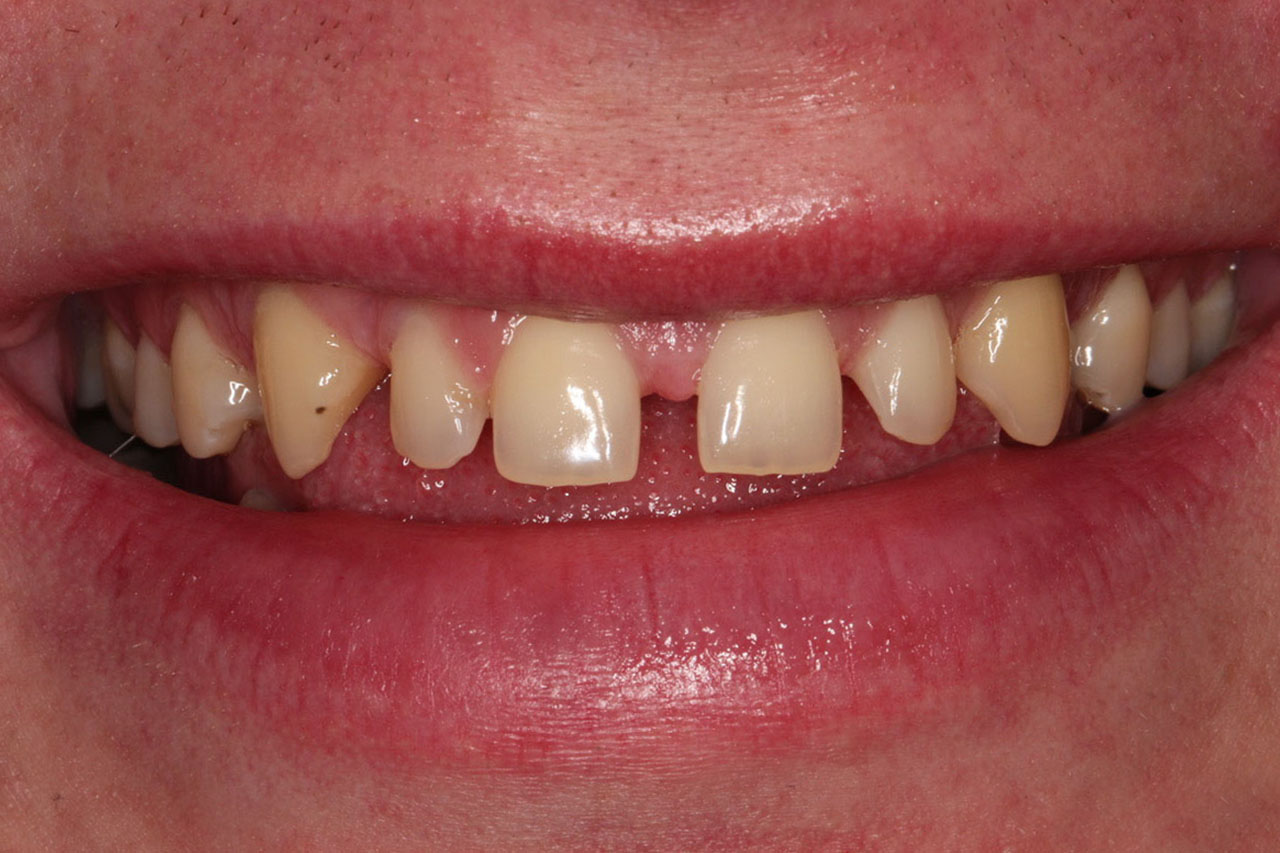

3. Licówki w celu zamknięcia szpar między zębami